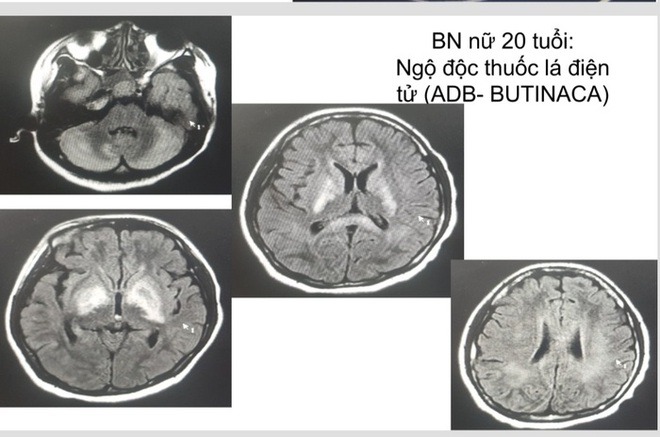

04/05/2024 02:28Báo động tình trạng khẩn cấp do thuốc lá điện tử, thuốc lá mới: Nhiều học sinh, thanh thiếu niên phải cấp cứu do ngộ độc, loạn thần

Nhiều thanh thiếu niên nhập viện vì ngộ độc chất ma túy trộn thuốc lá điện tử

Theo chia sẻ của TS.BS.Nguyễn Trung Nguyên - Giám đốc Trung tâm Chống độc, Bệnh viện Bạch Mai, ngày nào Trung tâm Chống độc cũng có bệnh nhân ngộ độc thuốc lá điện tử được điều trị tại đơn vị, trong đó rất nhiều trường hợp là học sinh, thanh thiếu niên phải cấp cứu do ngộ độc chất ma túy trộn thuốc lá điện tử. Các ca ngộ độc thuốc lá điện tử đều vào viện với biểu hiện co giật, kích thích, vật vã, ảo giác, loạn thần, hôn mê, tổn thương não và nhiều cơ quan khác, để lại di chứng nặng nề với sức khỏe.

Theo lời kể của người nhà, bệnh nhân có dùng thuốc lá điện tử được cho thêm hương liệu mới (do shipper giới thiệu), đến 05 giờ sáng ngày hôm sau bệnh nhân lên cơn co giật, sùi bọt mép, co giật toàn thân. Bệnh nhân được đưa đi cấp cứu ở Bệnh viện tuyến trước nhưng không đỡ, sau đó được chuyển đến Trung tâm Chống độc. Xét nghiệm mẫu thuốc lá điện tử bệnh nhân mang đến phát hiện chất ma túy cần sa tổng hợp là ADB-Butinaca.